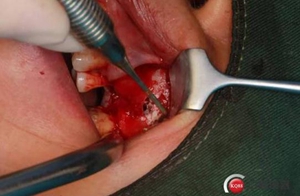

改良式外提升工具盒-外提 科貿(mào)嘉友收錄

大家好,我是梁老師的助理小依。由于梁老師每天手術(shù)檔期安排較滿,加上經(jīng)常出差講課,沒(méi)有時(shí)間整理病例 。為了方便大家更及時(shí)的了解梁老師最新手術(shù)動(dòng)態(tài),以后將由我為大家整理并推送梁老師最新經(jīng)典案例。案例文字旁白少,但圖片會(huì)盡量完整展示手術(shù)全過(guò)程,供大家學(xué)習(xí)參考。有任何問(wèn)題,可以留言,梁老師會(huì)親自為大家解答。感謝大家對(duì)梁老師的支持和關(guān)注!